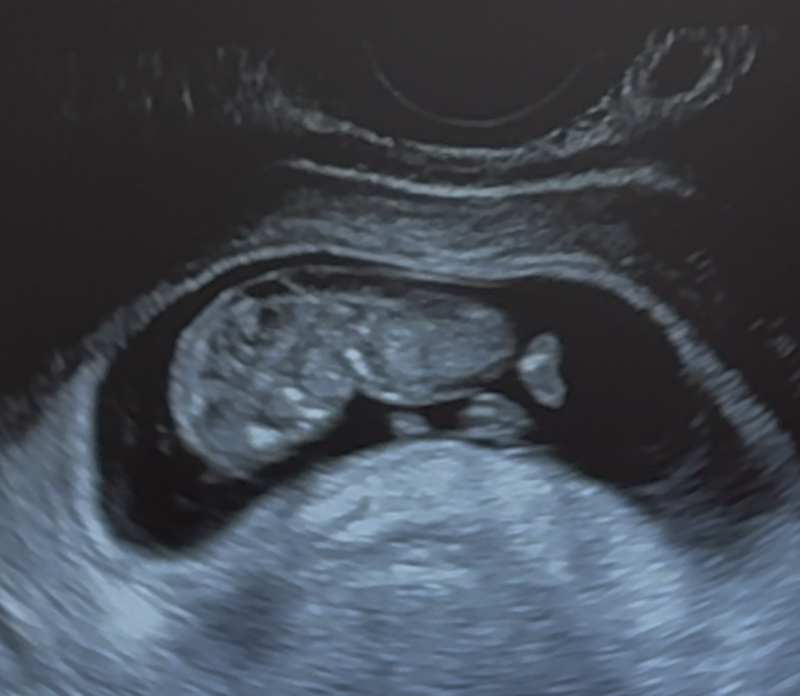

現在妊娠10週4日なのですが、初回妊婦健診の際のエコーで首後ろの浮腫が気になりました。

これはやはりntなのでしょうか??